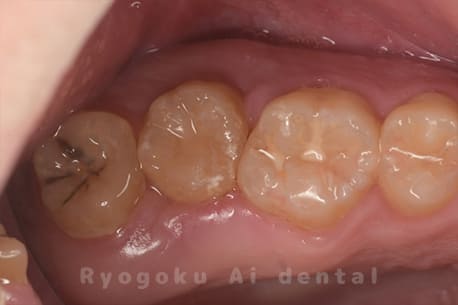

Case27

-

重度カリエス

歯牙移植術直後咬合面

歯牙移植術後咬合面

歯牙移植術前側面

歯牙移植術中側面

歯牙移植術後側面

部分矯正術前咬合面

部分矯正術中咬合面

部分矯正術後咬合面

部分矯正術前側面

部分矯正術中側面

部分矯正術後側面

- 原因

- 重度カリエス

- 治療内容

- 自家歯牙移植、部分矯正

- 治療費用

- 220,000円(移植費用)

110,000円(部分矯正費用)

虫歯が大きく、保存不可能となった歯を上の親知らずと交換する自家歯牙移植を行いました。移植歯が小ぶりであったため、部分矯正を行い問題なく噛み合い、経過良好です。